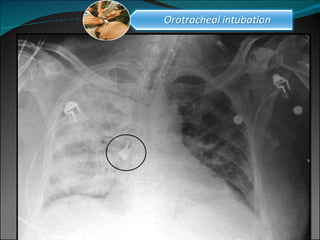

“ Patients do not die from a "failure to intubate."  'They die either from failure to stop trying to intubate  or from undiagnosed esophageal intubation.” Scott, DB Endotracheal intubation: friend or foe Br Med J (Clin Res Ed). 1986 Jan 18;292(6514):157-8.

“ Patients donot die from a &quot;failure to intubate.&quot; 'They die either from failure to stop trying to intubate or from undiagnosed esophageal intubation.” Scott, DB Endotracheal intubation: friend or foe Br Med J (Clin Res Ed). 1986 Jan 18;292(6514):157-8.